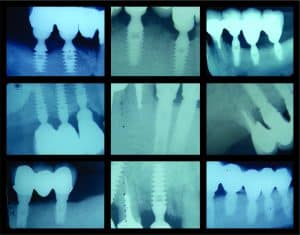

There are many situations where a patient might want to save their remaining natural teeth and not have them extracted. Natural teeth support the muscle attachments of the lips and face. Removal of natural teeth might therefore result in a permanent distortion of the lips or face. Loss of anterior (front) natural teeth can also occasionally cause changes in one’s speech. Whenever it is possible, remaining strong teeth roots should be saved by combining them with dental implants for additional support and stability. In cases involving loose teeth as a result of periodontal disease, adding strategically placed dental implants can remove some of the bite pressure off these teeth. This can possibly help remaining teeth last much longer in the mouth.